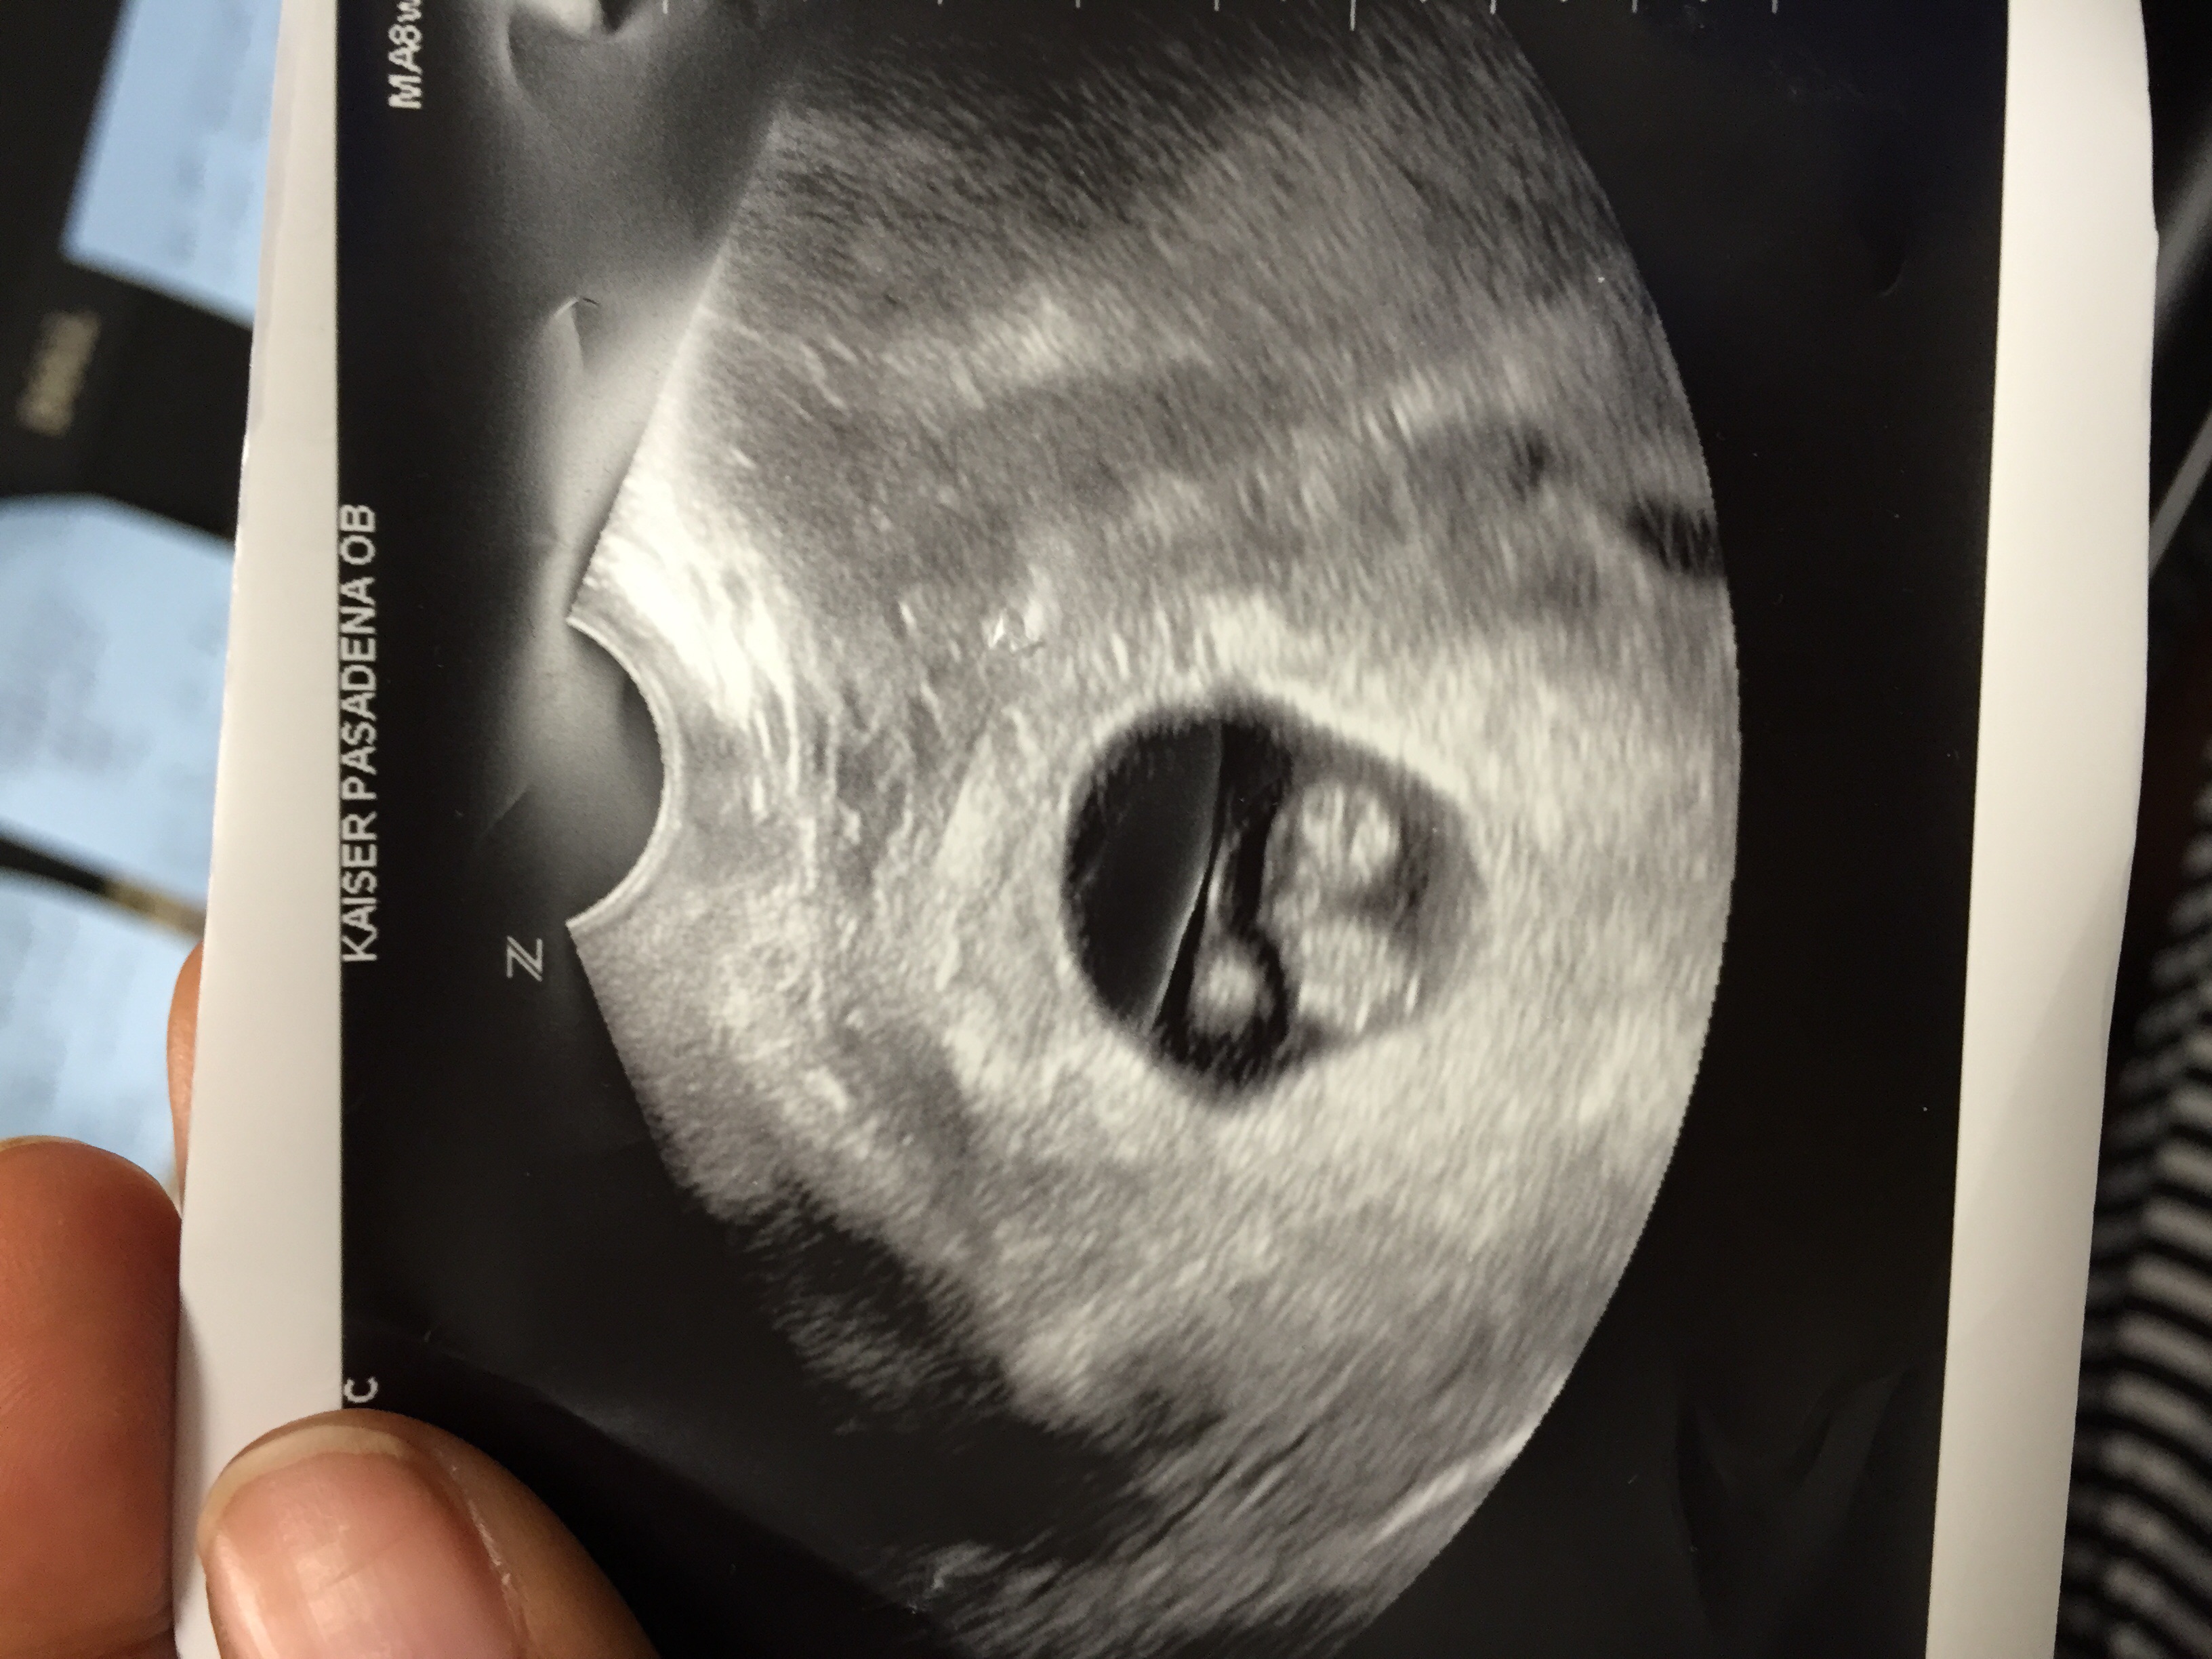

Yup, HG so I needed IV fluids, sublingual Zofran, and IV Reglan with a script for Diclegis. Oh, and an U/S! Check out this beefy nugget!

Soooo excited to finally get to post my u/s of our little chicken nugget. 8 weeks 1 day. Got to see the little heart beat flicker as well as hear the beautiful sound of the heartbeat. Such a surreal moment, one of the top moments of my entire life.